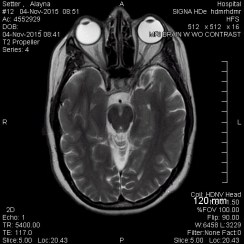

On November 04, 2015 I had an MRI; they found out that I had a brain tumor and I was officially diagnosed with Cushing’s Disease, a rare condition that had gone undiagnosed for 17 years and caused me extreme health issues. As I researched the disease, I found out that the symbol, or mascot, for Cushing’s is a zebra. This is because in medical school, when they talk about Cushing’s they tell med students that they’ll probably never see a Cushing’s case, so when they see symptoms that look like Cushing’s, they should consider other more common diagnoses instead. The saying is, “When you hear hooves, think of a horse, not a zebra.”